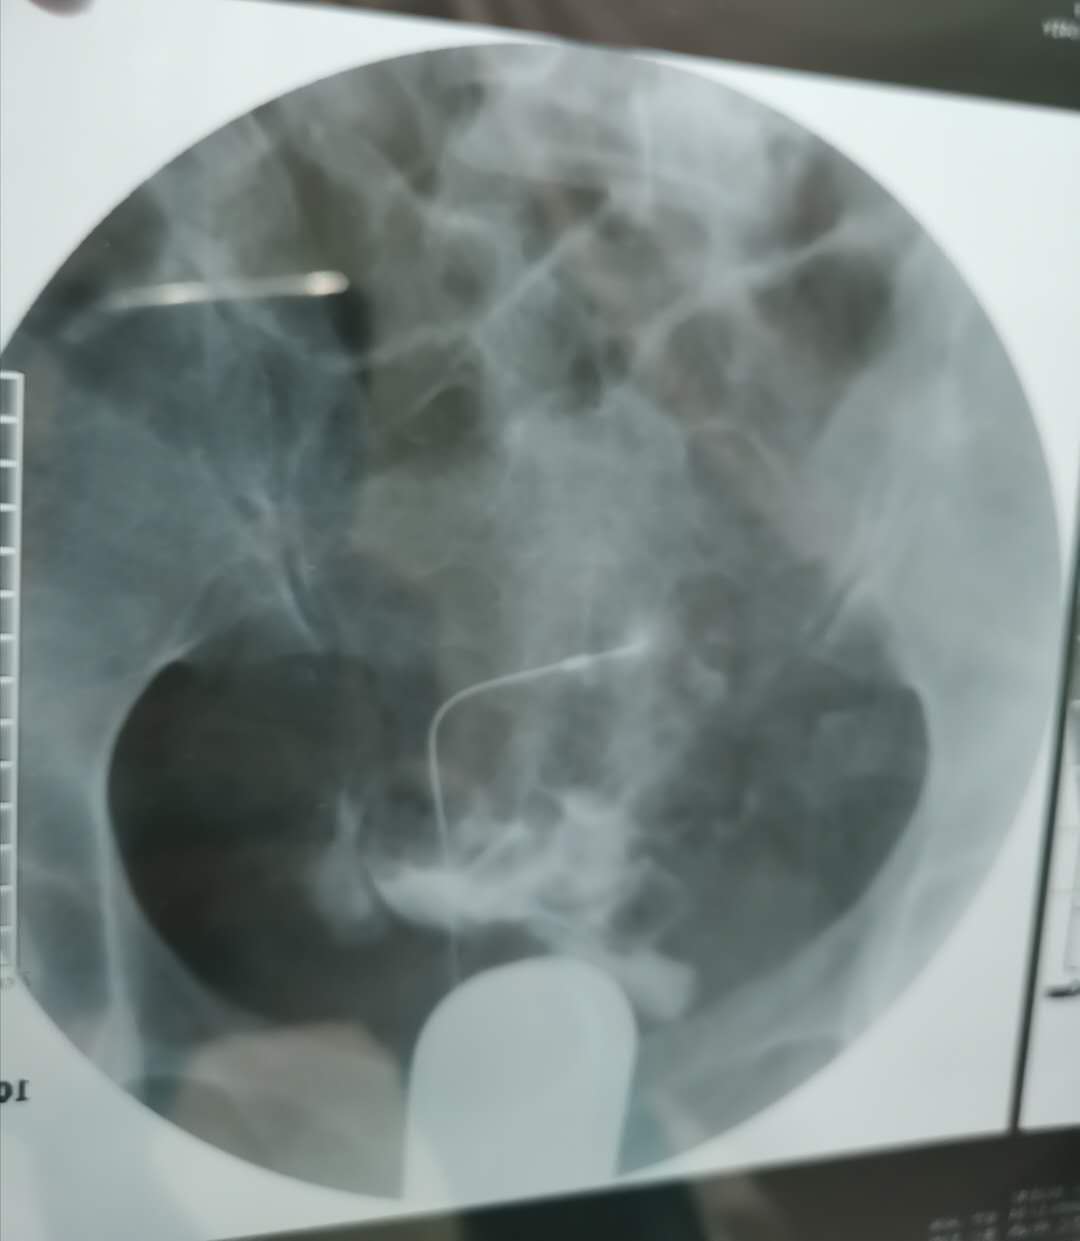

我这个是做了输卵管介入手术,请问输卵管是通了